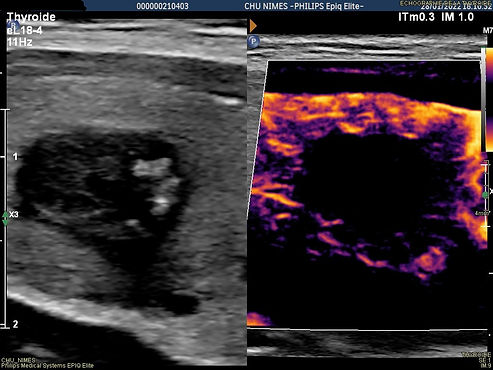

l'échographie montre un nodule thyroïdien kystique et hémorragique du lobe droit .

nodule hémorragique 25.2 cc avant alcoolisation

contrôle échographique 3 heures après l'alcoolisation avant de laisser partir la patiente

un contrôle échographique réalisé 3 mois après l'ablation montre une régression quasi complète du nodule avec un volume résiduel de 0.31 cc soit une diminution volumétrique de 98.37 %